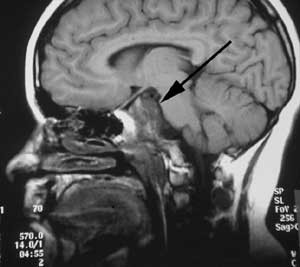

Pasient 2. Ni år gammel gutt med normal psykomotorisk utvikling frem til åtte års alder. Han utviklet da vekstretardasjon og det ble senere påvist en generell hormonsvikt og økende synstap. Radiologisk utredning viste en stor cystisk tumor i hypofyseregionen med affeksjon av synsbaner og hypothalamus. Tumor ble oppfattet som et kraniofaryngeom.

Det ble utført en stereotaktisk punksjon av cysten med instillasjon av radioaktivt yttrium. Man oppnådde imidlertid ikke tumorkontroll. Fire måneder senere utførte man derfor en kraniotomi og reseksjon av tumor. Under inngrepet viste det seg umulig å redde restsyn og hypofysefunksjon. Videre utviklet pasienten hydrocephalus postoperativt og fikk anlagt en ventrikuloperitoneal shunt.

I løpet av få måneder fikk gutten på nytt økende symptomer i form av hodepine, irritabilitet og personlighetsendringer. MR viste gjenvekst av tumor.

Pasienten ble henvist til Nevrokirurgisk avdeling, Rikshospitalet for vurdering med tanke på ytterligere kirurgi. Det forelå nå imidlertid en betydelig tumordestruksjon og invasjon i clivus av solide tumorkomponenter og ny cyste posterokaudalt mot 3. ventrikkel/hypothalamus og pons (fig 3a). Klinisk var pasienten også i meget rask forverring og hadde preoperativt redusert bevissthet, sløvet tale, ustø gange og urininkontinens.

Pasienten er ved tremånederskontroll betydelig restituert og har kun en mindre ekstremitetsparese. Som før den siste operasjonen er han blind og fullstendig hormonsubstituert. Postoperativ MR-undersøkelse viser ikke tegn til resttumor (fig 3b).